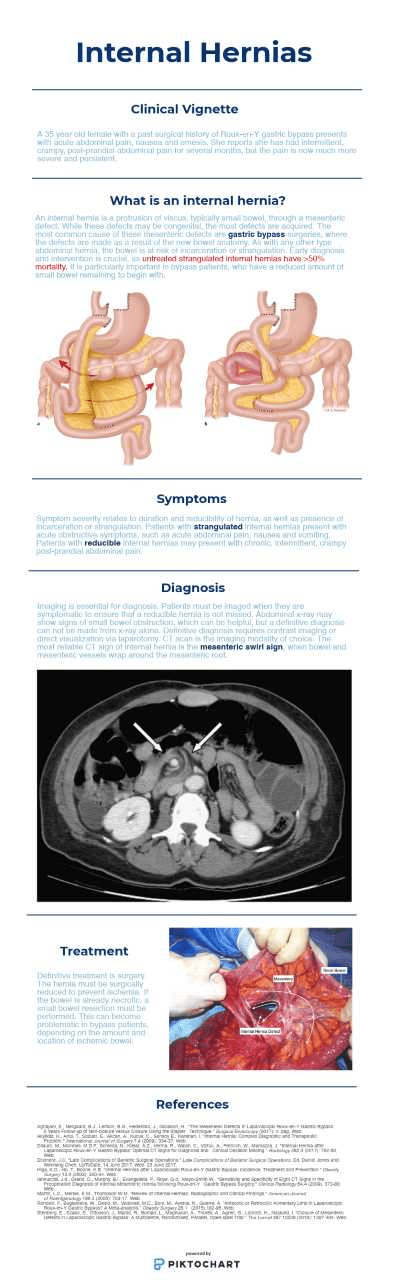

Internal Hernia June 23, 2018June 27, 2020 / myemresidency Amazing review of internal hernias by one of our rotators who matched into General Surgery! -Tom O’Hara MS4 Share this: Share on X (Opens in new window) X Share on Facebook (Opens in new window) Facebook Like Loading... Related